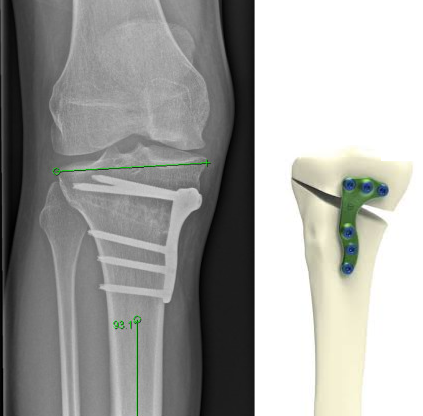

• L’ostéotomie : Cette opération consiste à changer l’alignement de l’os pour diminuer la pression sur la partie usée du genou. Elle est généralement proposée pour les patients jeunes dont l’arthrose n’affecte qu’une partie du genou, notamment avec des jambes arquées ou en X.

Après une ostéotomie, il faut attendre que l’os se consolide avant de pouvoir prendre appui dessus. Avec une prothèse, elle est immédiatement fixée sur l’os, donc on a le droit de marcher dessus immédiatement. Mais les muscles doivent récupérer de la chirurgie, donc on compte quelques semaines de béquilles et minimum 3 à 6 mois pour reprendre les activités de la vie normale.